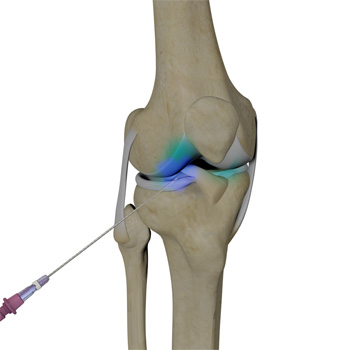

An intra-articular knee injection is a very effective form of treatment where medicine is delivered directly into the knee joint with the primary objective of relieving pain from conditions such as arthritis.

Intra-articular knee injections may be performed using various approaches. During the procedure, you will be seated or will lie on your back with the affected knee flexed or extended. The skin over the injection site is sterilized and numbed with a local anesthetic.

The needle is inserted into your knee joint and the medication is injected. In some cases, ultrasound imaging is used to help guide the needle to the correct site. You may feel some mild discomfort during the injection. In some cases, prior to injecting the medicine, a small amount of joint fluid is withdrawn to make space for the medication. Once the fluid is removed, the same site is used to administer the intra-articular injection. A small dressing is then applied over the injection site to complete the procedure.